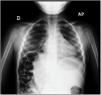

An ultrasound examination was performed due to suspicion of pneumonia (Appendix A, Video 1), evincing elevation of the diaphragm in the right hemithorax with subcostal interposition of bowel loops at the location of the liver and a small consolidation in the right middle lobe (Figs. 1 and 2). The radiographic features were suggestive of Chilaiditi syndrome (Fig. 3).

Chilaiditi syndrome is rare in children. Most cases are asymptomatic and are diagnosed due to a chance finding, in which case the condition is referred to as Chilaiditi sign. When the disease is symptomatic, patients present with breathing difficulty, vomiting, abdominal pain and constipation, and the condition is then referred to as Chilaiditi syndrome.